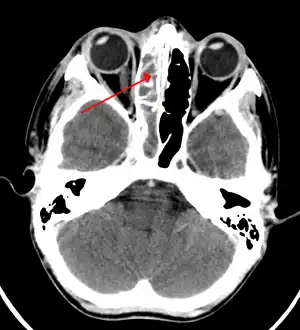

O processo de diagnóstico se inicia e muitas vezes é suficiente com uma história clínica bem colhida, associada a um exame físico bem feito. A critério médico podem ser utilizados exames radiológicos, como o raios X de seios da face, ou seios paranasais, destacando que para melhor identificação é recomendado uma tomografia computadorizada de seios perinasais.